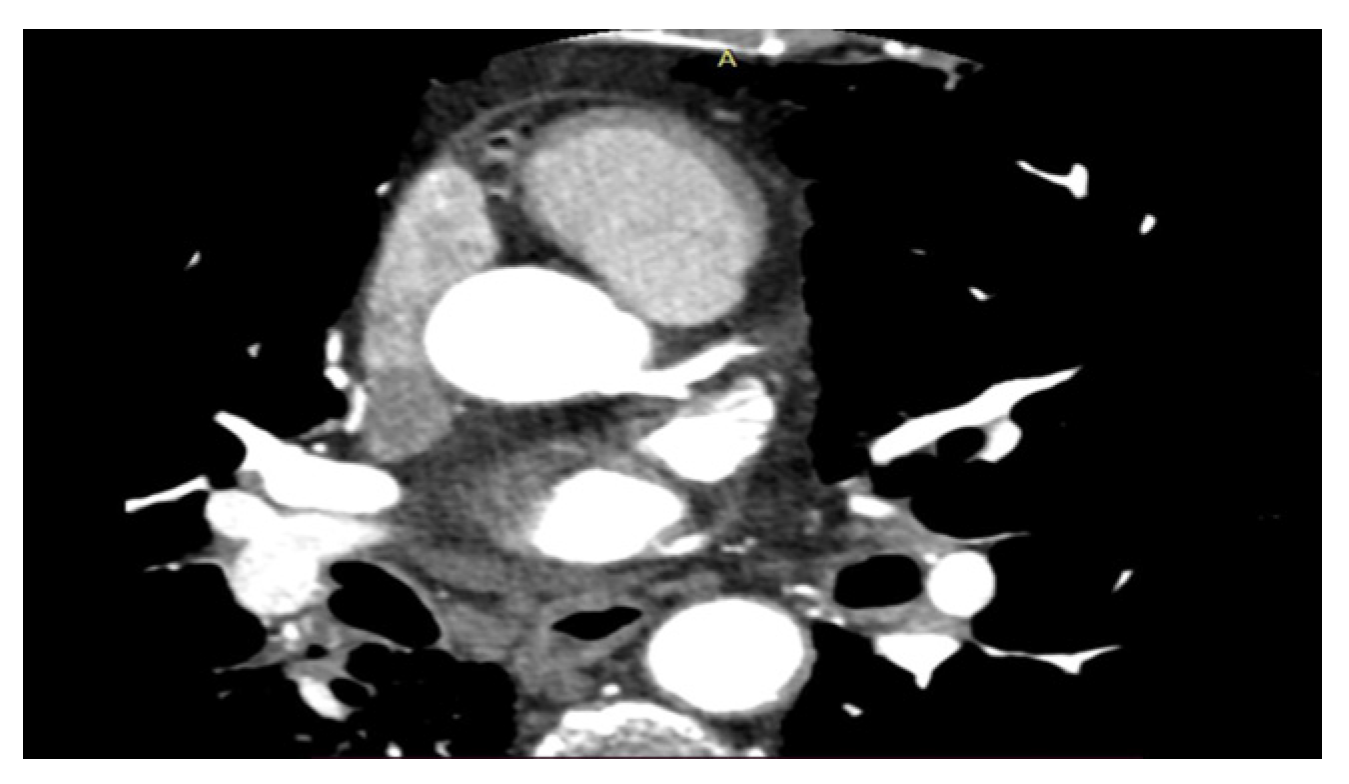

- CT parameters (calcium score, thrombosis, and calcified plaques)

2.6. CT Setting

| CT Settings | MR Settings |

| • Collimation 64 × 0.6 mm | • 1.5 Tesla Magnet |

| • Pitch 0.2 to 0.5 | • Slice thickness 8 mm |

| • Gantry rotation time 3.30 s | • Slice spacing 2 mm |

| • Pipe current 330 mA | • T1 FS sequences 10 min after the contrast agent injection |

| • Pipe power 120 kV (patient > 85 kg) or 100 kV (patient < 85 Kg) | • Prospective cardiac synchronization |

| • ROI threshold 100 HU | |

| • Slice thickness 1.0 mm |